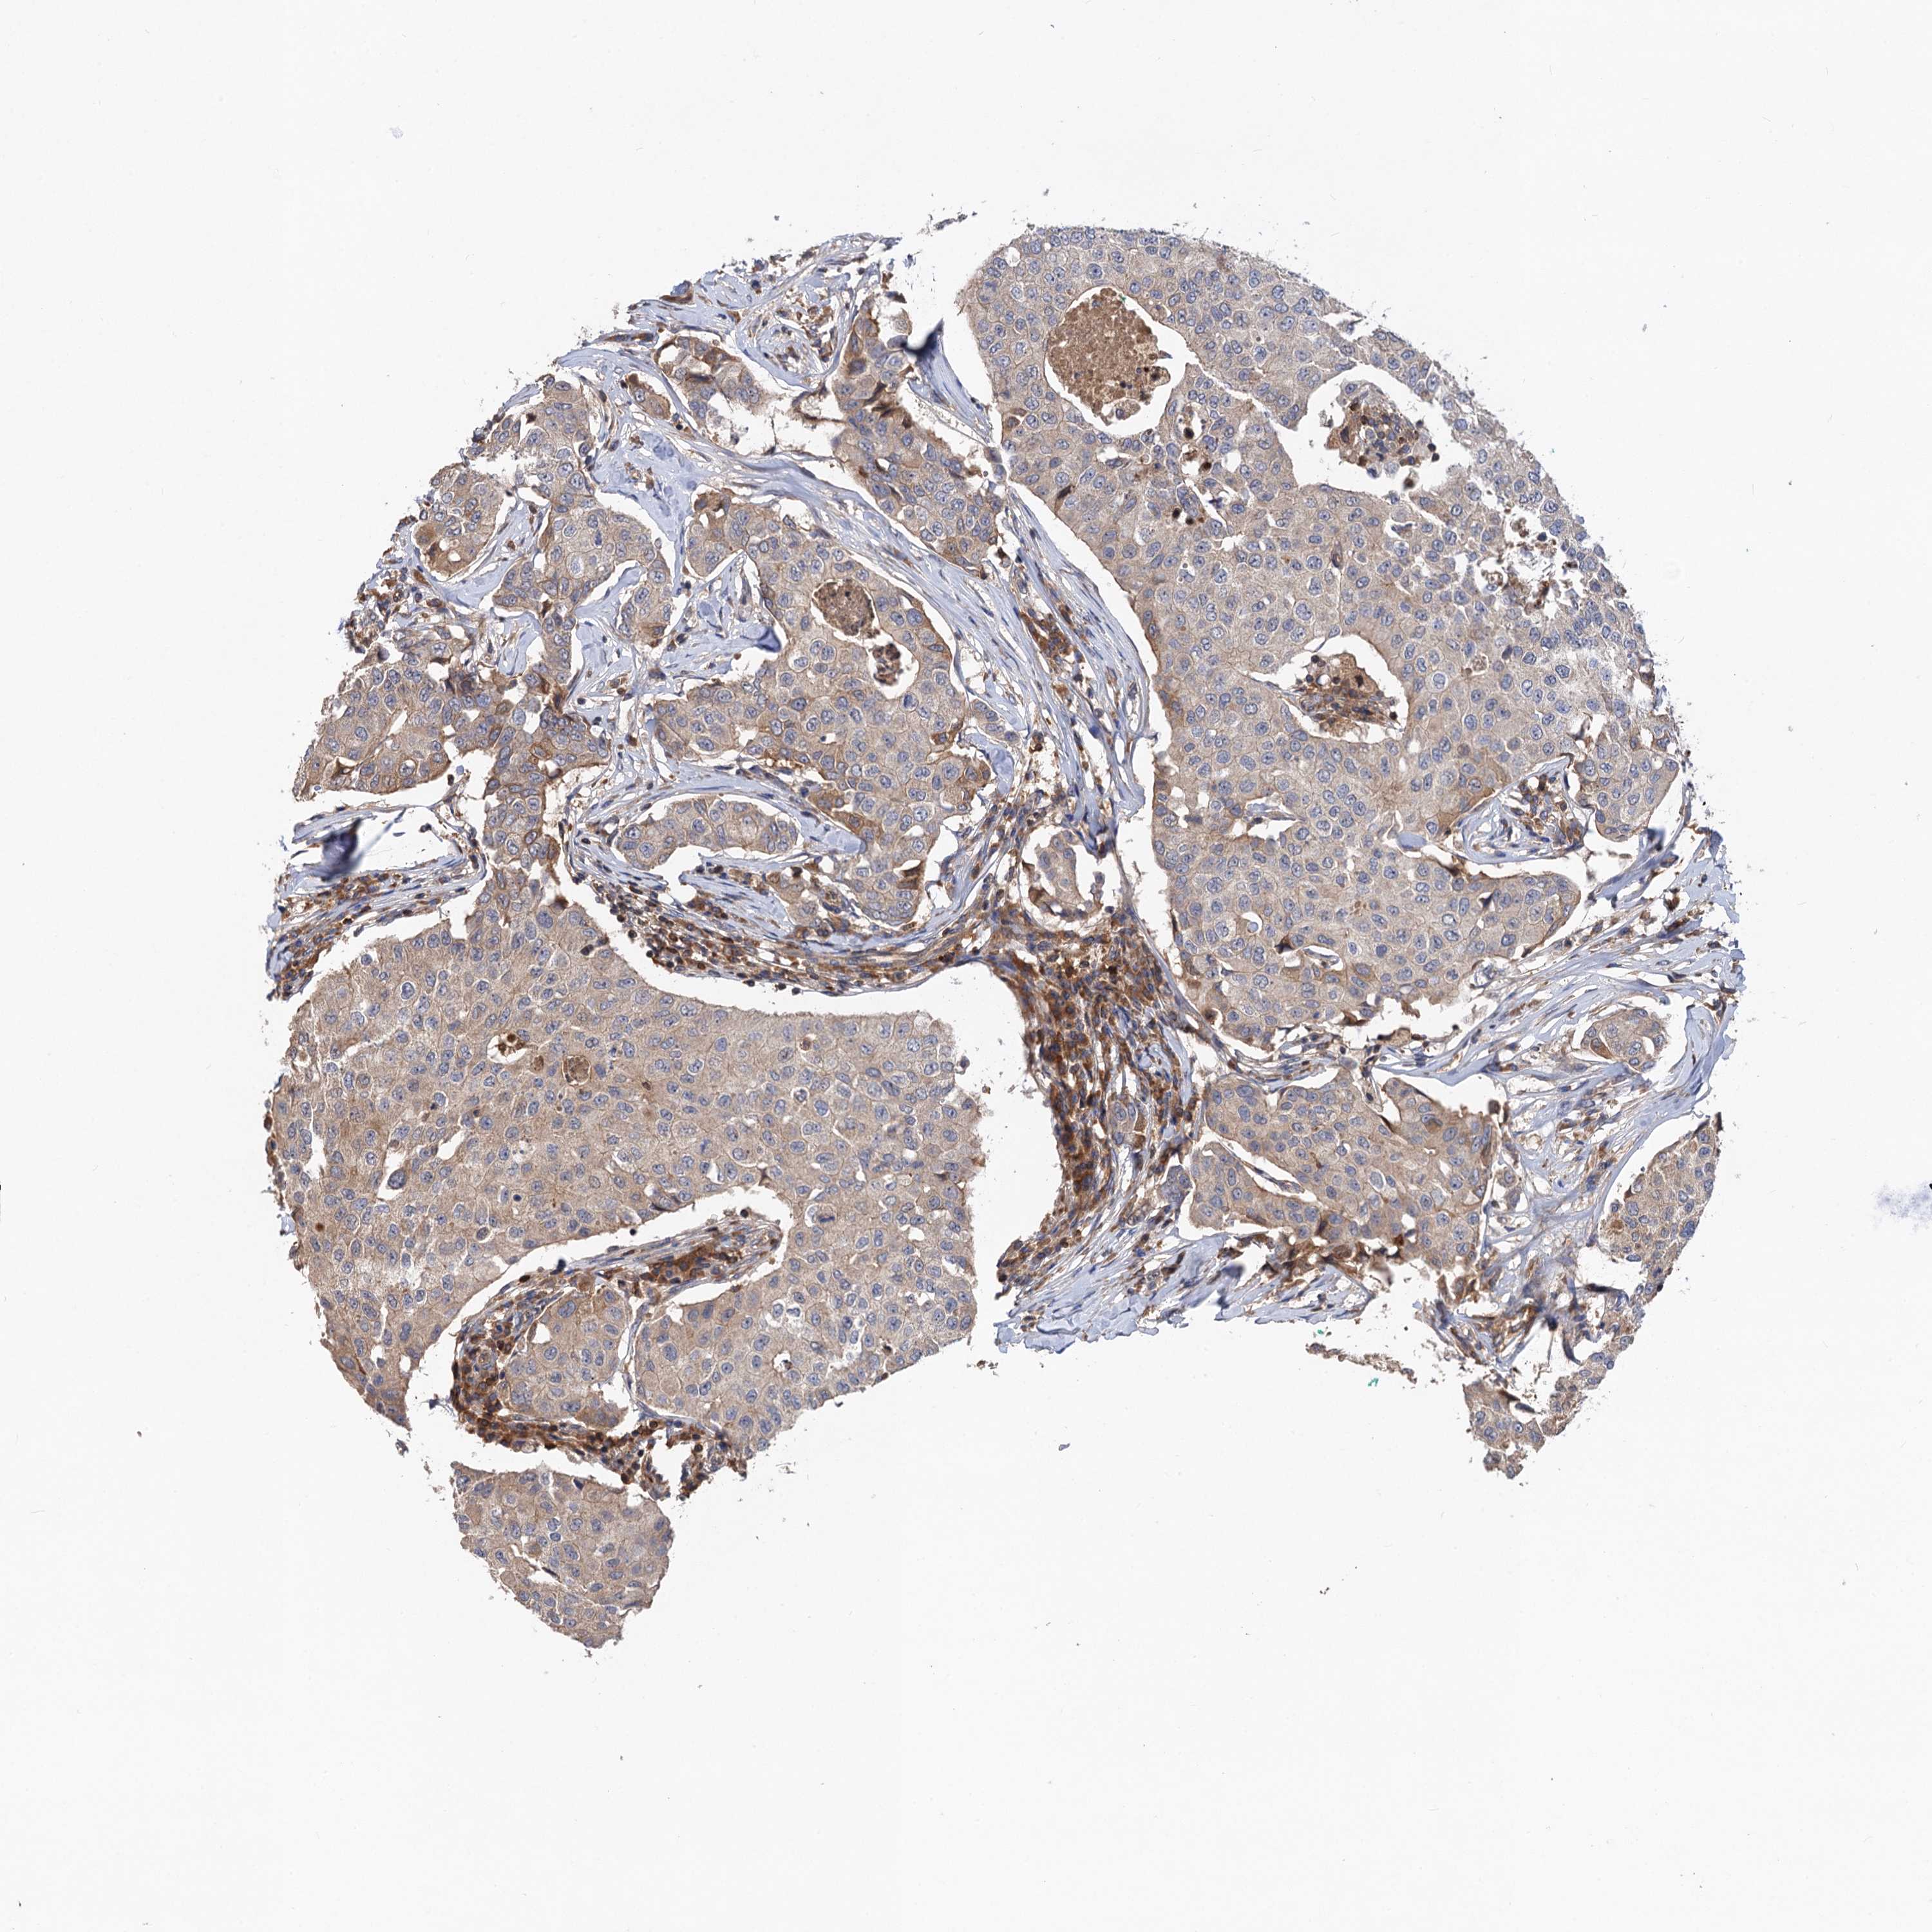

CANCER BREAST CANCER Show tissue menu

Breast cancer

Human cancer